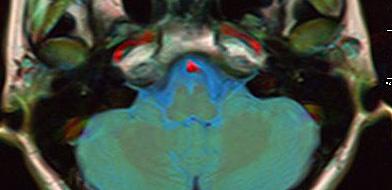

Контрастный раствор заполняет просвет артерий и вен, а также межклеточные пространства в исследуемом участке, благодаря чему на снимках чётко виден рисунок сосудистой сети, а также аномалии (например, петли, анастомозы, аневризмы и др.). Также при наличии вазоневрального конфликта можно визуализировать зону компрессии корешка черепно-мозгового нерва.

Использование контрастного вещества позволяет выявить опухоли диаметром менее 3 мм. Ткани опухоли накапливают контраст, и в зависимости от степени их злокачественности сосудистая сеть имеет характерный рисунок. На основании полученных изображений рентгенолог может предположить природу процесса, однако окончательный диагноз ставит лечащий врач.